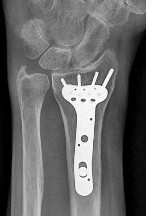

- الأشعة السينية (X-rays): هي الخطوة الأولى في تقييم الكسور، الخلوع، وتغيرات التهاب المفاصل. تساعد في تحديد مدى تدهور العظام والمسافات المفصلية. على سبيل المثال، تُظهر صور الأشعة السينية كسور السلاميات

. - الأشعة المقطعية (CT Scan): توفر صوراً تفصيلية ثلاثية الأبعاد للعظام، وهي مفيدة جداً لتقييم الكسور المعقدة، مثل كسور العظم الخطافي (Hamate Hook Fracture) التي قد لا تظهر في الأشعة السينية العادية